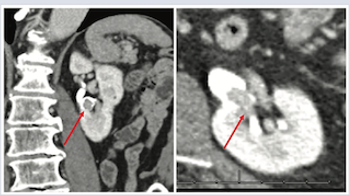

A 21-year-old male presented to the emergency department for evaluation of testicular pain and swelling 5 days after being struck in the groin.